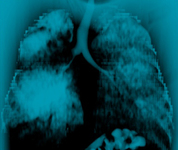

Malignant endobronchial obstruction on multidetector chest CT: mediastinal window demonstrating right mainstem malignant obstruction

From the collections of Jose Fernando Santacruz MD, FCCP, DAABIP and Erik Folch MD, MSc; used with permission